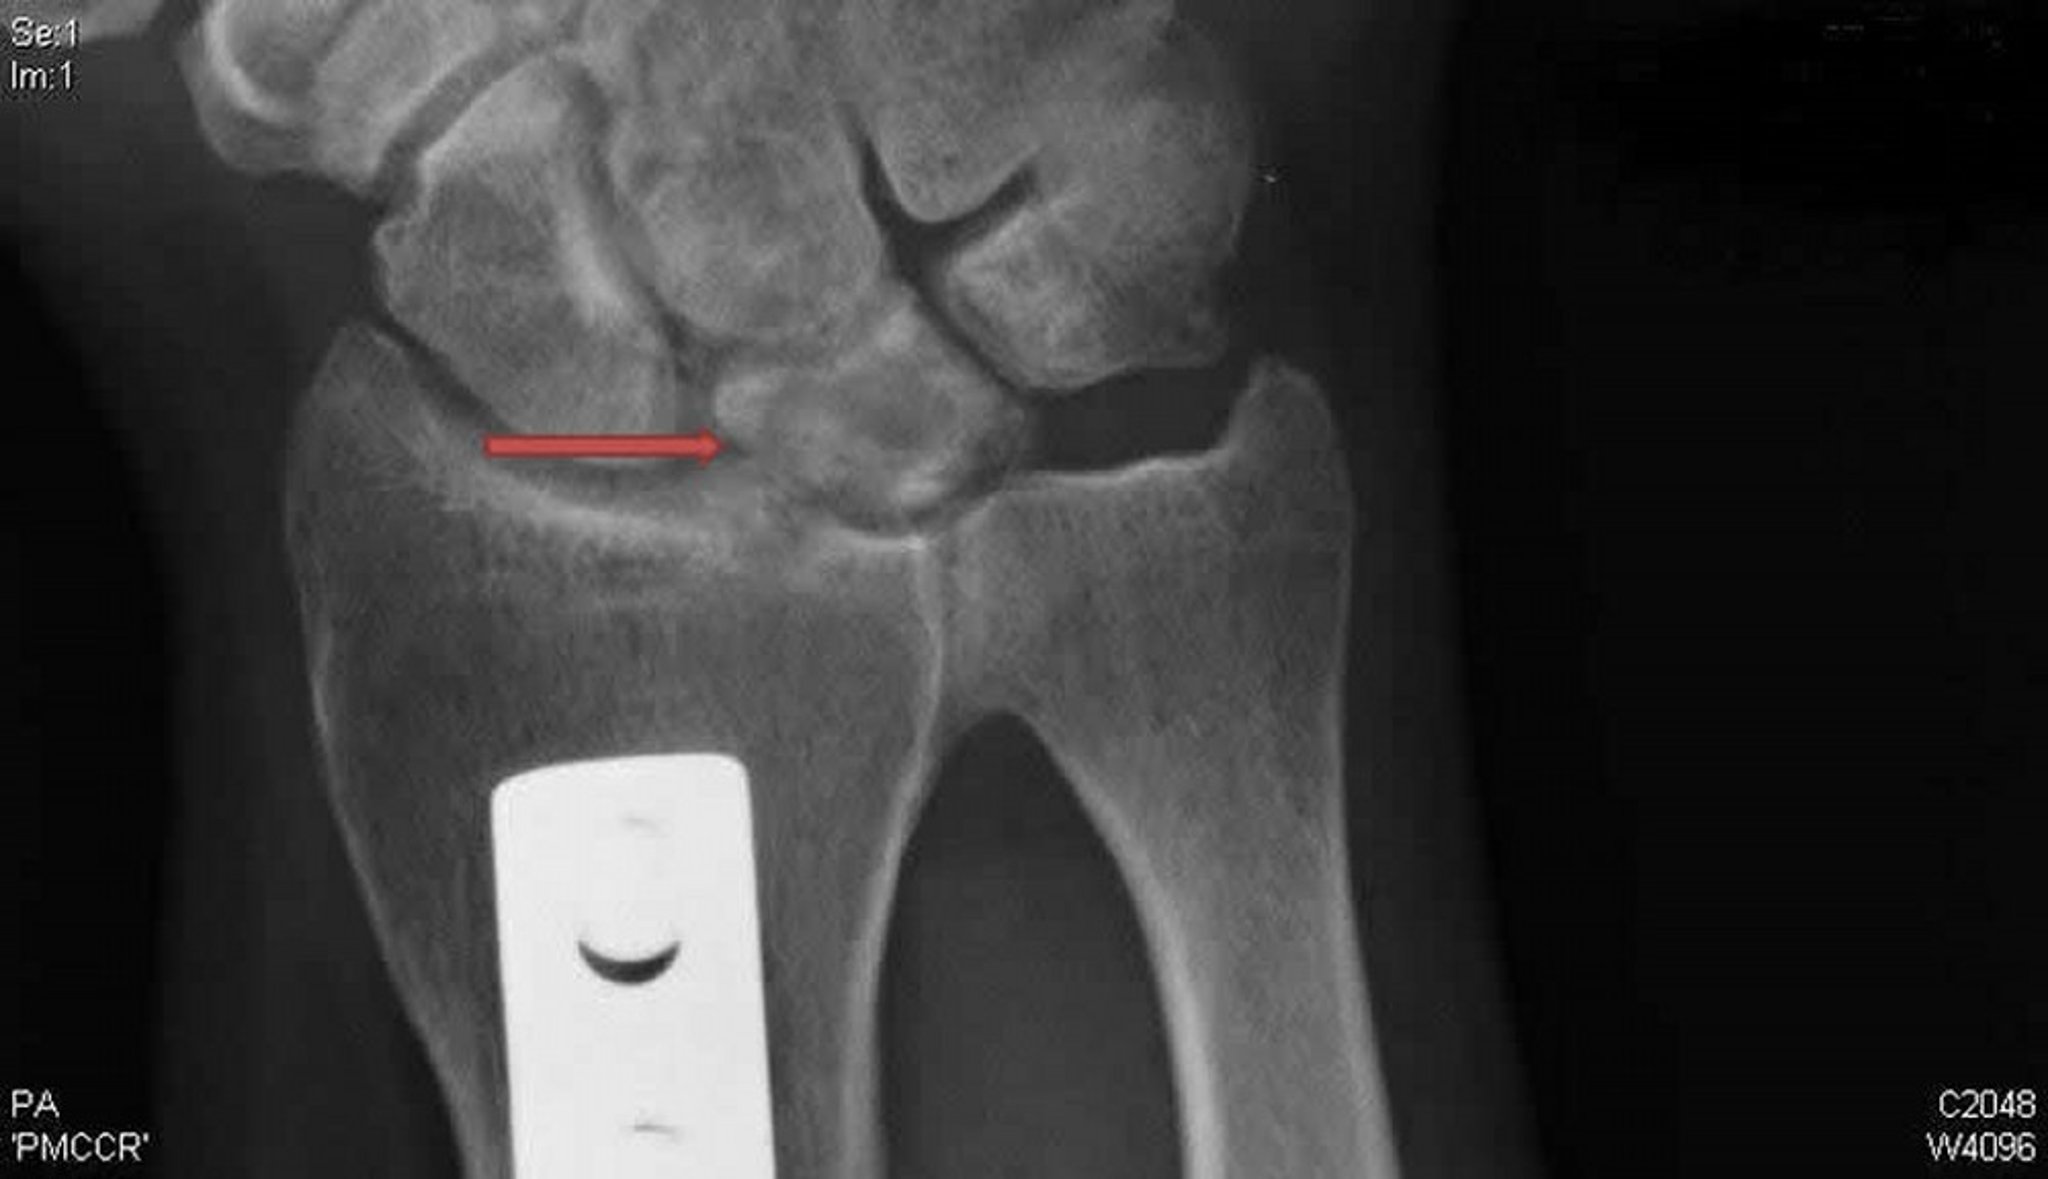

Kienböck Disease (Posteroanterior Radiograph)

This posteroanterior radiograph of the right wrist shows cysts and sclerosis of the lunate bone (arrow) typical of Kienböck disease. The metal plate is evidence of a radial shortening osteotomy that was done in an effort to unload the lunate and potentially treat this condition.

Radiograph courtesy of David R. Steinberg, MD.